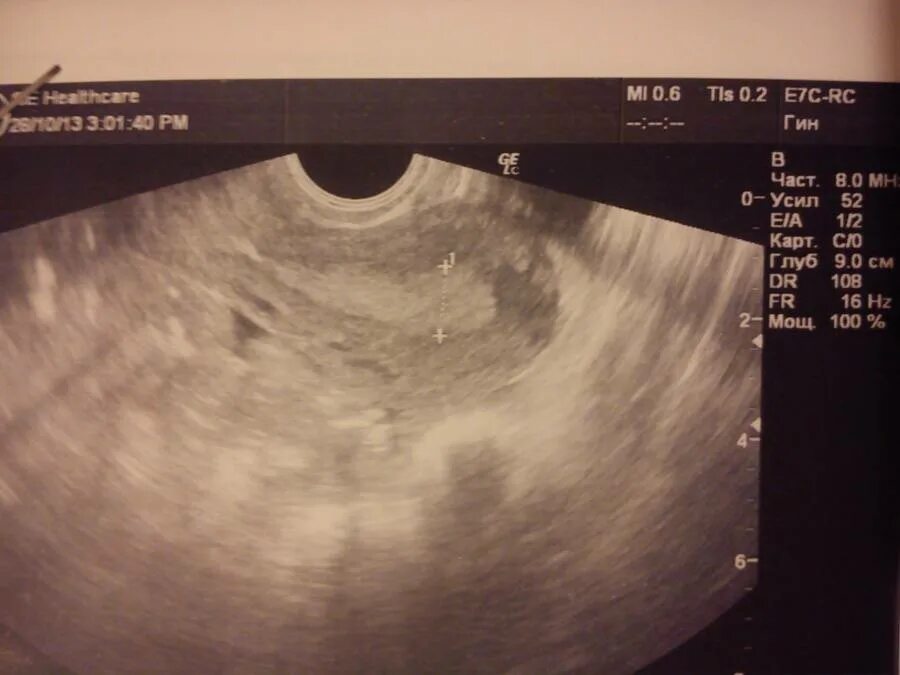

Как выглядит беременность на 1 неделе